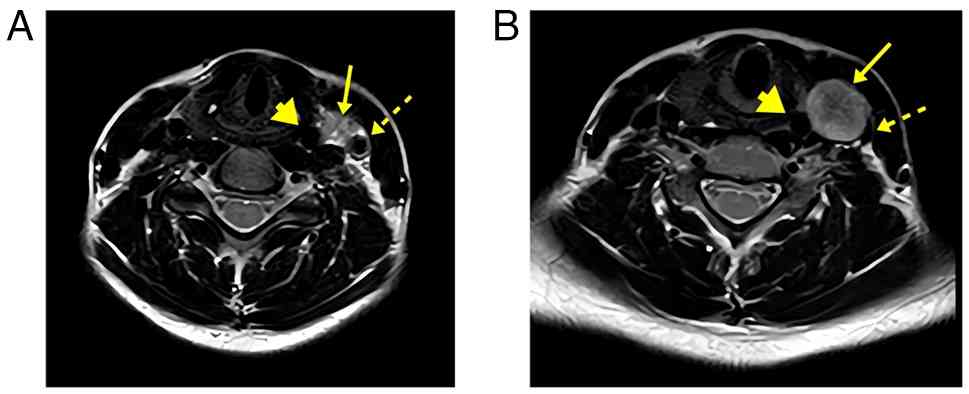

An ultrasonography revealed a well-defined heterogeneous mass (21-22x17-24 mm) located between the carotid artery and internal jugular vein, with internal vascularity and posterior venous displacement. Magnetic resonance imaging (MRI) demonstrated a rounded mass with intermediate-to-high T2 signal intensity anteromedial to the carotid bifurcation, causing characteristic vascular displacement and carotid bifurcation splaying (Fig. 1). These imaging features closely mimicked those of a paraganglioma and resulted in an initial radiological misdiagnosis, highlighting the diagnostic challenge associated with CVS. A laboratory evaluation revealed mild leukocytosis (white blood cells, 13.2x109/l), neutrophilia (74%), thrombocytosis (520x109/l) and elevated levels of inflammatory markers (erythrocyte sedimentation rate, 65 mm/h; C-reactive protein, 44 mg/l). Routine biochemical parameters, including liver and renal profiles, thyroid function (thyroid stimulating hormone, 2.1 µIU/ml) and metabolic markers, were all within normal limits (Table I). The case was reviewed in a Multidisciplinary Oncology Team (MDT) meeting, where surgical excision was recommended as the definitive management approach. A chronological summary of the clinical course of the patient, as well as the investigations performed and the progression of her condition is presented in Table II.

(A and B) Axial non-contrast MRI

images demonstrating a well-defined, rounded mass lesion with

intermediate to high T2 signal (arrow). The lesion is located

anterior to the left common carotid artery (dotted arrow), below

the level of its bifurcation, causing splaying of the common

carotid artery (dotted arrow) and the internal jugular vein

(arrowhead). It measures 20x17 mm in axial dimension.

Figure 1

(A and B) Axial non-contrast MRI images demonstrating a well-defined, rounded mass lesion with intermediate to high T2 signal (arrow). The lesion is located anterior to the left common carotid artery (dotted arrow), below the level of its bifurcation, causing splaying of the common carotid artery (dotted arrow) and the internal jugular vein (arrowhead). It measures 20x17 mm in axial dimension.